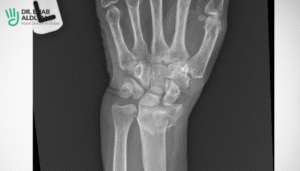

Scaphoid fracture

A scaphoid fracture is an injury that happens in the wrist when a small bone near the thumb breaks or cracks. This bone has a poor blood supply, which makes it prone to delayed healing and complications such as failure to heal or bone death.

A scaphoid fracture may not show up on an initial X-ray, so your doctor may require additional tests like an X-ray, a CT scan, or an MRI to confirm the diagnosis. A scaphoid fracture usually requires a cast or surgery to fix the bone and prevent further damage.